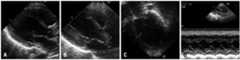

Fig. 2.

Initial echocardiography showing a markedly dilated left ventricle (LV) on the parasternal long axis view (A) with mitral valve regurgitation through a coaptation site without significant left atrial enlargement (B). Spherical LV on the subcostal 4-chamber view (C) with increased EPSS on M-mode echocardiography (D).

A corrected age 2-month-old female infant presented to our hospital with poor feeding and irritability for 7 days. The patient appeared pale and dusky on initial assessment. The infant was delivered prematurely at our hospital with a birth weight of 2.45 kg (50-75 percentile) and a height 47 cm (75 percentile) at 34+3 weeks of gestation (Fig. 1 A), and had an uneventful clinical course thereafter. There was no history of recent viral infection or family history of cardiac disease. The patient's body weight on admission was 5.1 kg (10-25 percentile) and height 60 cm (75-90 percentile). The patient exhibited signs and symptoms of shock with blood pressure 54 mmHg (in systole) and 31 mmHg (in diastole), heart rates 200 beats per minute, respiration rates 60 per minutes, body temperature 36.6℃. Chest roentgenogram showed unilateral haziness of the entire left lung and suspected cardiomegaly, while the right lung field appeared to be normal (Fig. 1 B). Echocardiography revealed a massively dilated left ventricle (LV) with poor contractility (Fig. 2 A). There was also evidence of severe atrioventricular valve regurgitation (Fig. 2 B), and the LV chamber appeared spherical in shape while the left atrium was not grossly enlarged (Fig. 2 C). The patient's LV ejection fraction (EF) was estimated to be 24.5%, with a diastolic LV inner diameter of 41.3 mm, end point septal separation of the anterior mitral valve of 17.3 mm (Fig. 2 D), and spherical index of 0.92 (reference; 0.60-0.73) (Table 1). No anatomical abnormalities of the coronary arteries were noted. In contrast to the markedly elevated N-terminal pro brain natriuretic peptide of > 35000 pg/mL and severe anemia with a hemoglobin of 6.5 g/dL, other cardiac enzymes including serum glutamic oxaloacetic transaminase, creatine phosphokinase, lactate dehydrogenase, creatine phosphokinase-MB, troponin-T, and C-reactive protein remained within normal limits throughout the patient's hospital stay (Table 2). Retrospective review of the chest roentgenogram taken at birth revealed equivocal cardiomegaly (Fig. 1 A), but no abnormal cardiopulmonary signs or symptoms were noted with respect to the previously recorded vital signs.

Fig. 4.

Echocardiographic images correspondingly matched withFig. 2 each showing normal ellipsoid left ventricle configuration after 12 months of treatment on the parasternal long axis view without mitral valve regurgitation or left atrial enlargement (A and B) and on the apical 4-chamber view (C) with improved wall motion on M-mode echocardiography (D).